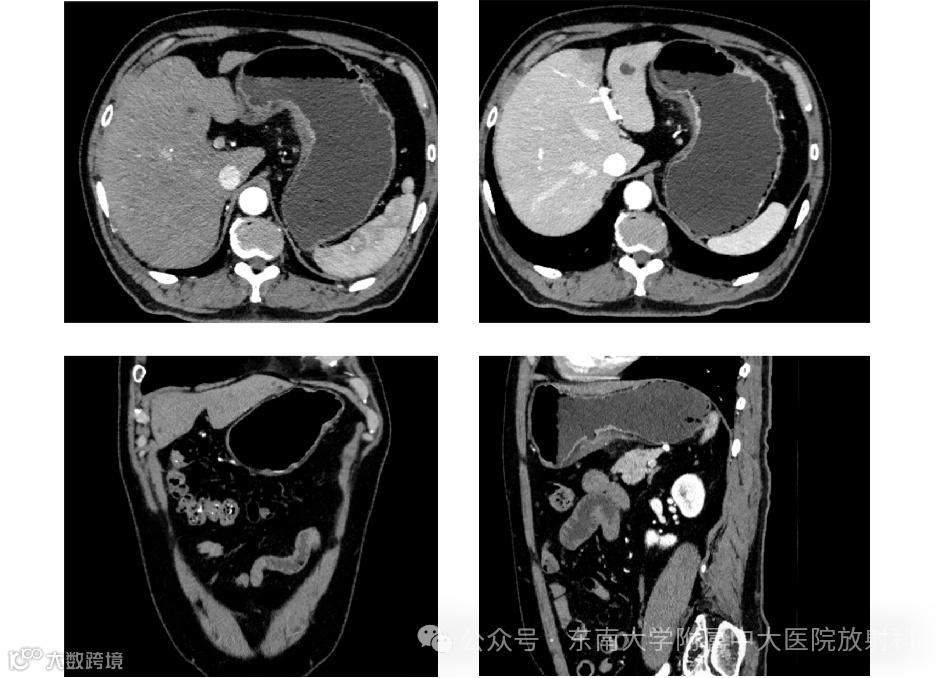

病例4

男,78岁

主诉:左上腹疼痛 1 月余

现病史:患者一月余前无明显诱因下出现左上腹烧灼样疼痛,伴反酸嗳气,休息后疼痛可缓解。无腹胀腹泻, 无排尿困难,无畏寒寒战,无呕血黑便,无咳嗽咳痰,无胸痛气喘,无胸闷心悸,无呼吸困难等不适。患者至天长市人民医院就诊,查胃镜(2024-05-21)示:胃体粘膜见一隆起性病变。病理(2024-05-23)示:中低分化腺癌,伴印戒细胞癌。患者为求进一步诊治,于我院就诊,拟“胃恶性肿瘤”收住我科。病程中,患者神志清, 精神可,食纳可,睡眠良好,大小便正常,近期体重无明显增减

影像学检查